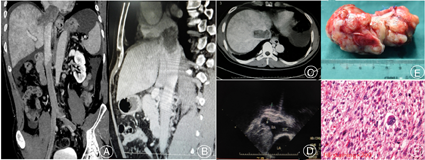

病例二:患者,男性,46岁,因活动后气喘伴双下肢麻木1月余入院,平素无高血压、冠心病,行CTV检查示:下腔静脉肝静脉至右心房入口处肿瘤(见封四,图2Ⓐ,图2Ⓑ,图2Ⓒ),行经食管超声见右心房下腔静脉汇入处见高回声肿块影(见封四,图2Ⓓ)、胸部及全腹部MRI平扫+增强等检查,联合心脏外科、肝胆胰外科医师手术,进腹后见肝脏淤血严重,探查见下腔静脉肿瘤来源于肝静脉汇入部,侵及肝右静脉,向上生长侵及右心房,肿块质硬,行右股静脉、下腔静脉、升主动脉插管体外循环。于肝右静脉内侧肿瘤表面切开肝脏,逐渐分离出肿瘤前壁、远端和肝右静脉,纵行切开心包、下腔静脉至肝右静脉,完整切除肿瘤(见封四,图2Ⓔ)。因为肿瘤侵及肝右静脉、下腔静脉前壁及右心房后壁,所以切除了1/3肝右静脉前壁及下腔静脉前壁,间断性阻断第一肝门。术后病理结果显示:平滑肌肉瘤(见封四,图2Ⓕ)。术后行CTV检查,发现下腔静脉肝上段狭窄(考虑重建下腔静脉时翻转肝脏后复位引起下腔静脉扭转)。

注:Ⓐ:肝静脉汇入部至右心房入口处下腔静脉肿瘤;Ⓑ:肝静脉汇入部至右心房入口处下腔静脉肿瘤;Ⓒ:肝静脉汇入部下腔静脉肿瘤,并侵及右肝静脉;Ⓓ:经食管超声见右心房下腔静脉汇入处见高回声肿块影;Ⓔ:完整切除肿瘤,质地较坚硬,呈灰红色;Ⓕ:平滑肌肉瘤术后病理图(苏木精-伊红染色,×200)。